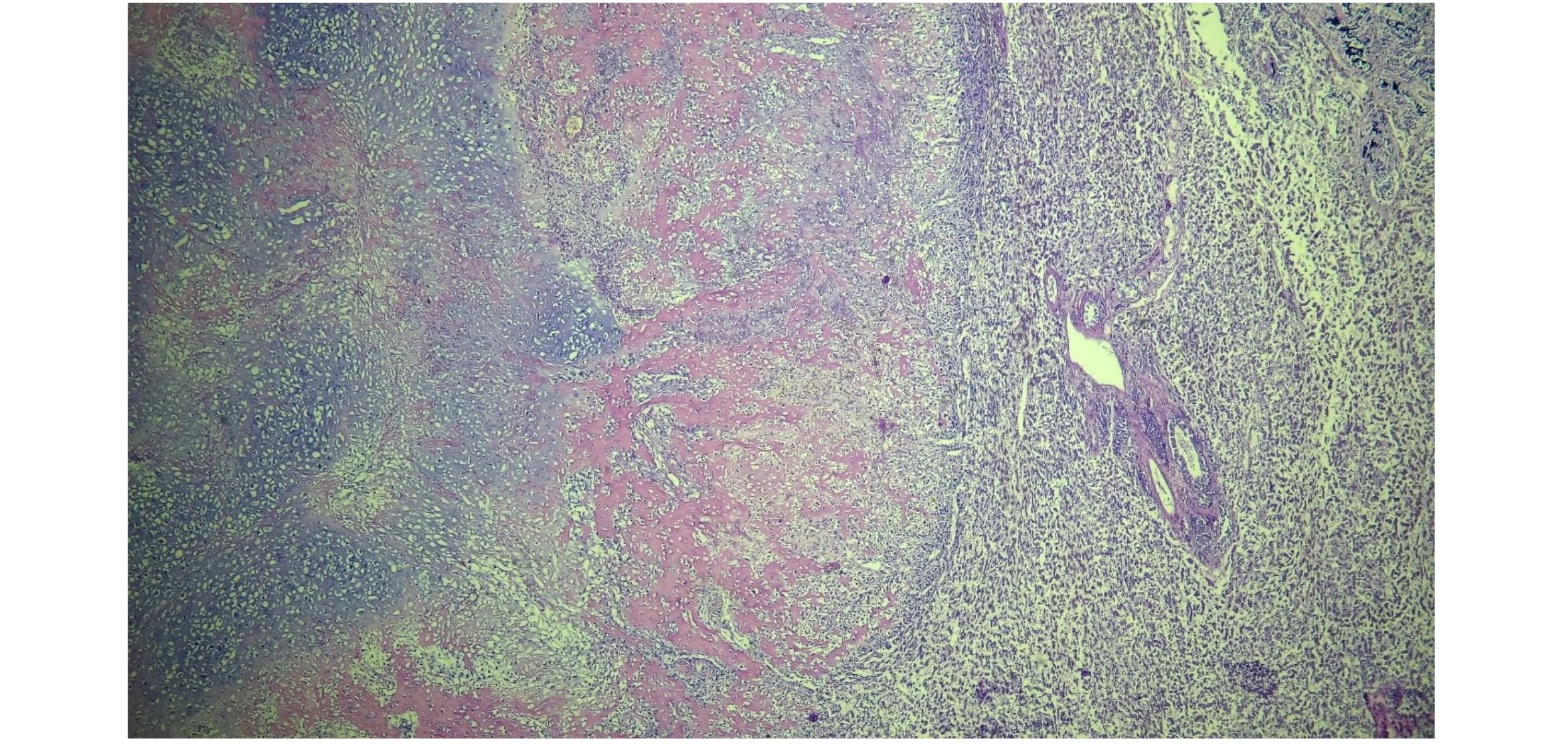

Besides not possible to visualize in macroscopy, the lungs also presented the same microscopic examination of all the regions (Fig.2): a marked cellular infiltrate been irregular, multifocal and non-encapsulated. The cells exhibited an irregular tubule-papillary arrangement, sometimes isolated amidst intense fibrocollagenous stroma. They were polyhedral to elongated, intermediate in size, with moderate to scarce, eosinophilic, vacuolated to homogeneous cytoplasm. They had a rounded, centralized nucleus with coarsely dotted chromatin and 0 to 3 intermediate and conspicuous nucleoli. Marked anisokaryosis, anisocytosis and moderate cellular pleomorphism were observed. The neoplasm exhibited low mitotic activity, with 7 mitotic figures observed in 2.37mm², with moderate binucleated and multinucleated cells (Fig.3). Additionally, presence of an intense multifocal to coalescent necrosis and intense, multifocal bone and cartilaginous metaplasias (Fig. 4).

Figure. 2. Microscopic examination of the intestine (A), lung (B) and liver (C).